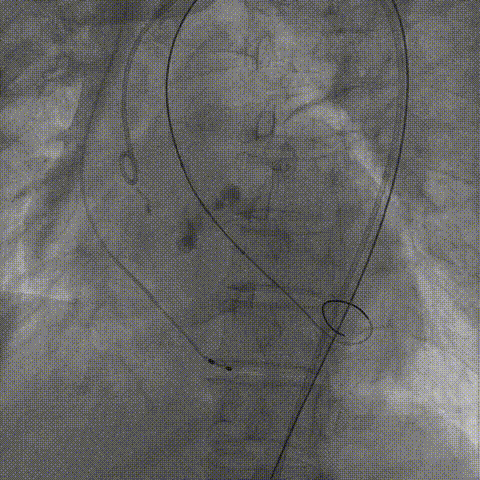

TaurusNXT植入过程

手术使用Z-Med 20mm球囊预扩两次,植入AV23 TaurusNXT主动脉瓣,Snare圈套器协助输送系统过弓、过瓣,120次/分起搏频率下,在左右重合位影像下释放瓣膜达到工作位,造影显示位置偏深,完全回收两次后释放达工作位,造影显示位置仍然不理想,之后第三次使用部分回收,精准释放瓣膜,之后使用Z-Med 20mm球囊后扩张两次。术后即刻超声心动图评估显示瓣膜位置良好,微量瓣周漏,主动脉瓣口峰值流速为1.90m/s,平均跨瓣压差为8mmHg,有效瓣口面积 1.60cm²,血流动力学指标理想。

部分回收后瓣膜定位释放

球囊后扩张

瓣膜最终造影